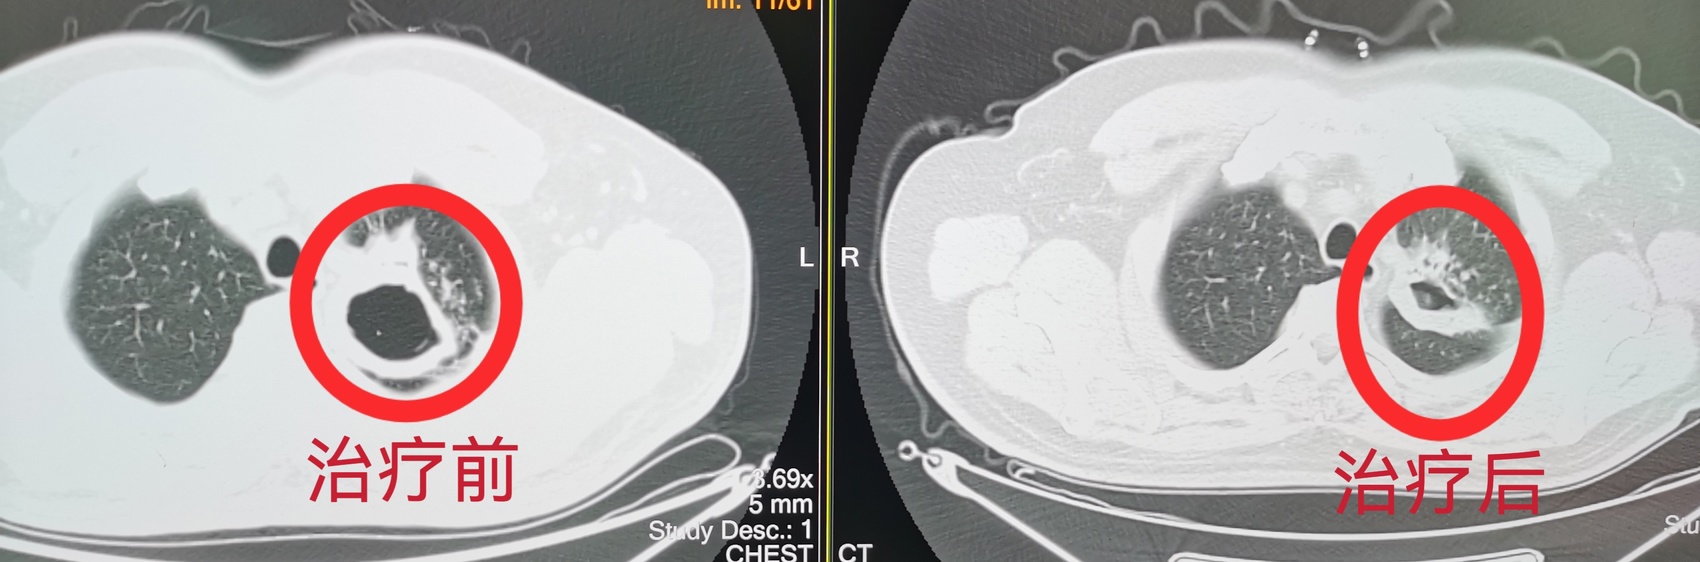

治疗前后空洞对比

今年10月,叶先生因咳嗽、低烧在基层医院进行CT检查,医生发现病灶,为了进一步确认,将叶先生的影像资料通过远程系统实时传至资阳市中心医院。

“远程影像不仅是技术的联通,更是诊疗闭环的构建与分级诊疗的落地实践。”资阳市中心医院相关负责人表示。该服务使得疑难病例能及时上转明确诊断,如发现肺结核、疑似肿瘤或脑血管异常等复杂情况后,可迅速引导患者进入上级医院进一步检查与治疗;而当诊断明确、病情稳定后,患者又可带着方案返回当地随访复查,实现了“基层首诊、上下联动”的高效医疗服务闭环。